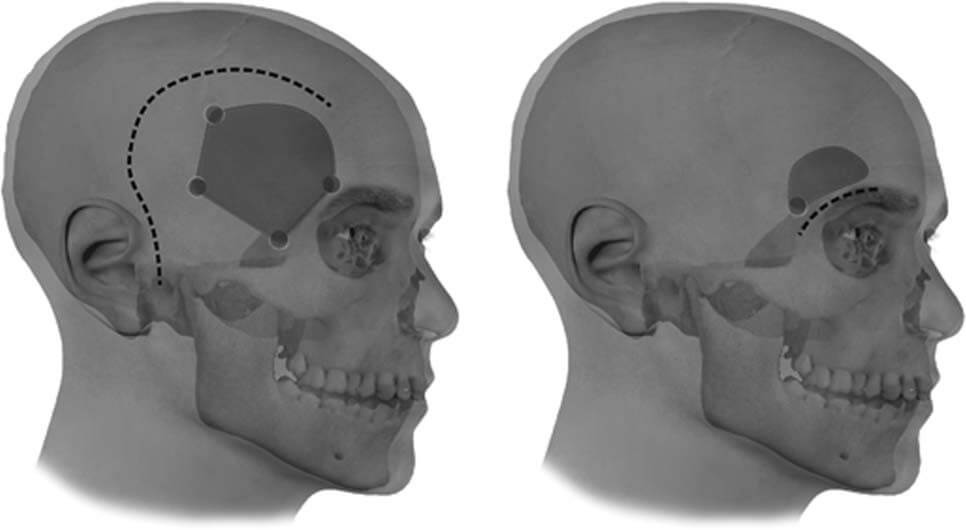

Τα σύγχρονα συστήματα νευροπλοήγησης ανέλαβαν την καθοδήγηση του νευροχειρουργού κατά τη θεραπεία ακόμα και των πιο δυσπρόσιτων βλαβών του εγκεφάλου μέσα από κρανιοτομίες λίγων τετραγωνικών εκατοστών (keyhole craniotomies) (εικόνα 1). Καλοήθεις (μηνιγγιώματα, ακουστικά νευρινώματα, αδενώματα της υπόφυσης, κρανιοφαρυγγιώματα, αιμαγγειοβλαστώματα) και κακοήθεις (αστροκυττώματα) όγκοι του εγκεφάλου, πρωτοπαθείς ή δευτεροπαθείς (εγκεφαλικές μεταστάσεις), ανευρύσματα και αρτηριοφλεβώδεις δυσπλασίες (AVMs) χειρουργούνται πλέον με τη βοήθεια του Νευροπλοηγού και των μικρονευροχειρουργικών εργαλείων κάτω από το χειρουργικό μικροσκόπιο.